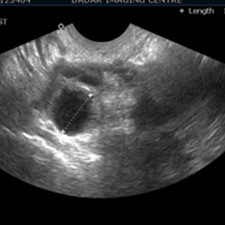

OFollicular Monitoring (फॉलिक्युलार मॉनिटरिंग) सोनोग्राफीच्या मदतीने अंडाशयाची होणारी वाढ बघणे

S.S.G(सोनोसालफिंगोग्राफी) गर्भाशयात विशिष्ट प्रकारचे औषध सोडून सोनोग्राफीच्या साहाय्याने गर्भाशय व नळयाची तपासणी